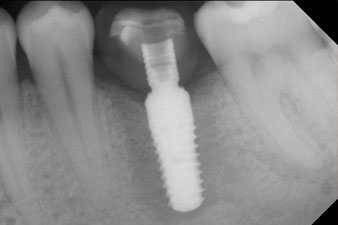

Имплантът е поставен както е планирано след цялостно отстраняване на гранулационната тъкан (blueSky, bredent).

Въртящият момент, използван за машинно-задвижвано поставяне, е 43 Ncm. Освен това, след завинтване на измервателния щифт (SmartPeg), специално пригоден за импланта, стойността на ISQ се измерва със сондата на W&H Osstell ISQ модула.

Този модул е допълнителна екстра към Implantmed на W&H и е закачен към имплантологичния мотор (виж фиг. 11). Липсата на ISQ стойност непосредствено след поставянето е 64 оровестибуларно и 68 мезиодистално (максимална стойност = 100).